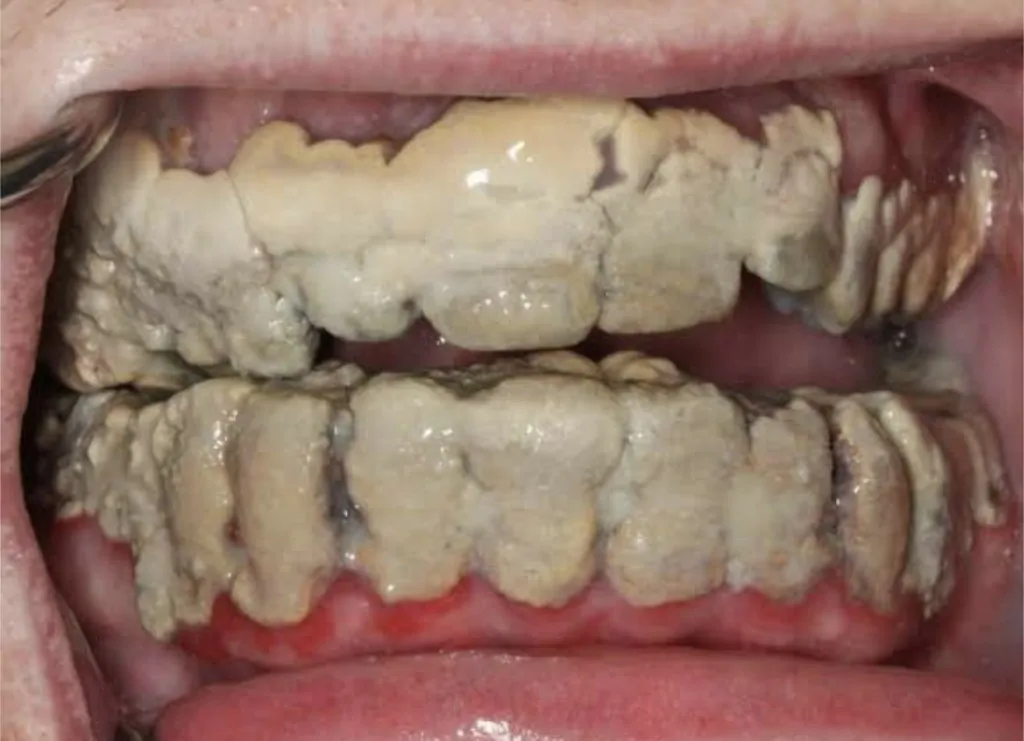

Karang gigi adalah masalah biasa di alami oleh kebanyakan orang terutamanya pada bahagian belakang gigi.

Pertumbuhan plak ini kerana campuran baki sisa makanan yang tidak dibersihkan dan air liur sehingga menyebabkan ia mengeras dan melekat pada gigi. Nak tengok, biasanya warnanya sedikit kuning berbanding dengan gigi kita.

Kelebihan Scaling Gigi yang seterusnya adalah bagi menghindari penyakit gusi. Mungkin ada rasa ia tiada kaitan tapi sebenarnya karang gigi boleh menyebabkan penyakit gusi seperti berdarah dan bengkak.

Jika tidak dirawat buat jangka panjang, boleh menyebabkan menjadi longgar atau nama lain kita panggil ‘Periodontitis’.